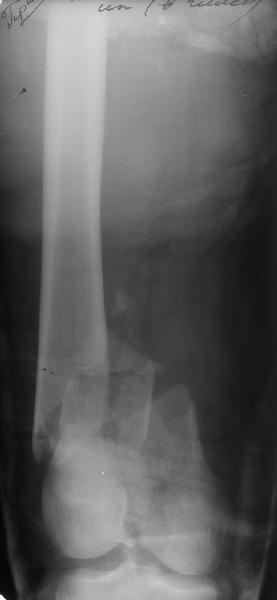

Такой вариант мы не рассматривали как чрезмерно травматичный. Как и предполагали, удалось сопоставить отломки стержня и после удаления

винтов вытолкнуть нижний кусок дистально. И через это же отверстие, используя стандартный доступ с расщеплением сухожилия 4-главой мышцы,

ретроградно забили другой стержень диаметром опять 11 мм - толще у нас пока таких нет. Обнадеживает то, что диаметр утолщенной части стержня 12 мм, а отверстие - 5 мм.